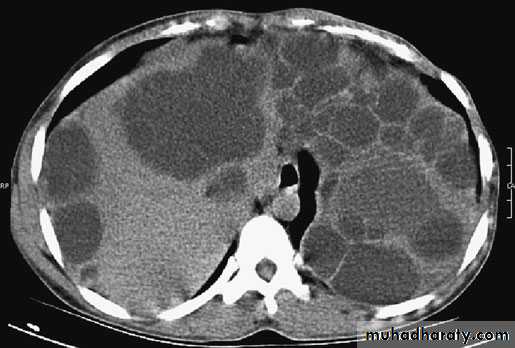

Ultrasound and CT scan are the investigations of choice. The CT scan shows a smooth space-occupying lesion with several septa .An ultrasound of the biliary tract may show abnormality in thegall bladder and bile ducts. Hydatid infestation of the biliary system should then be suspected.